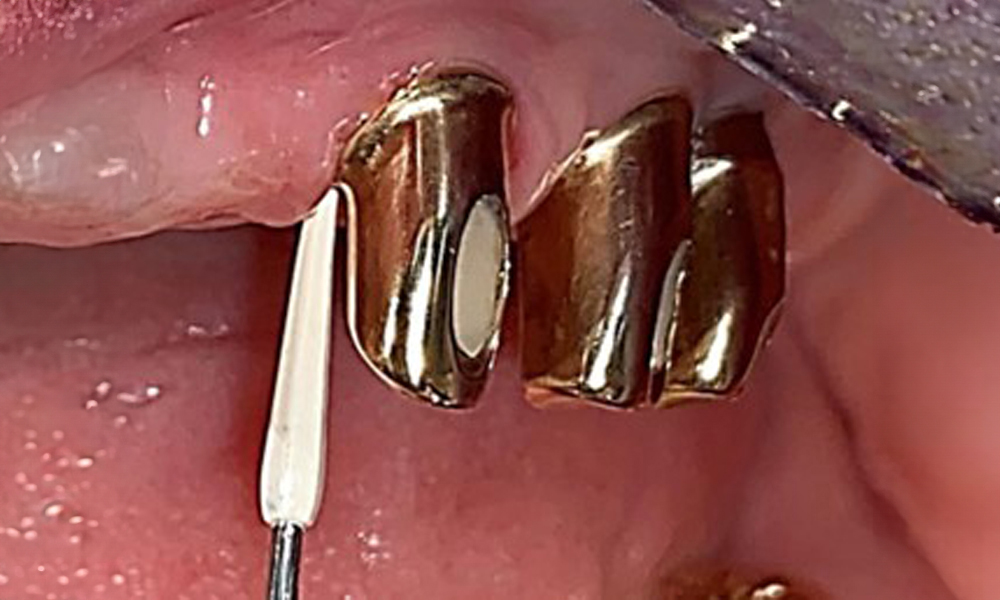

Okklusalansicht: Oberkiefer mit Zahn- und implantatgetragenen Teleskopen.

Abb. 2: Okklusalansicht: Oberkiefer mit Zahn- und implantatgetragenen Teleskopen.

Der dentale Befund stellt sich wie folgt dar: Kombinierte herausnehmbare Implantat- und zahngetragene Teleskoparbeit auf Implantaten 15, 13, 21, 23, 24, 25 und Zahn 11 (Abb. 1, Abb. 2, Abb. 3). Im Unterkiefer ist die Patientin mit einem festsitzenden Zahnersatz versorgt. 37–34 sowie 45–47 haben suffiziente Brücken (Abb. 4). Kronenränder sind intakt, aktive kariöse Läsionen sind nicht vorhanden. An Zahn 43 zeigt sich eine Compositefüllung mit Randspalt. Im Unterkiefer liegen Rezessionen mit freiliegender Wurzeloberfläche zwischen 1 – 3 mm vor. Dies trifft auch für 11 zu.